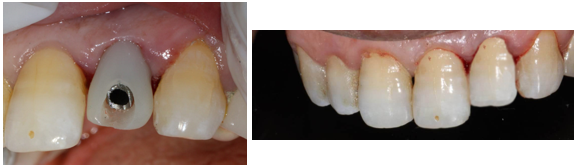

The crown was sealed and the patient is satisfied with her crown both aesthetically and functionally (Figure 16).

Figure 16. Sealing of the final prosthesis and final result of implant rehabilitation